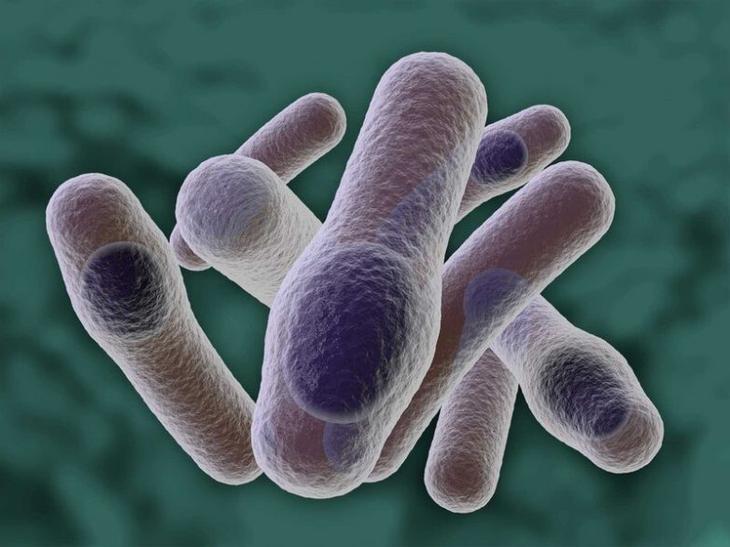

10. Mycobacterium tuberculosis, или палочка Коха

Бактерия, вызывающая туберкулез. Смертность чрезвычайно высока даже в наши дни: это заболевание входит в десятку ведущих причин человеческой гибели. Примерно четверть населения планеты имеет латентный туберкулез. Это значит, что заболевание может проявить себя в любой момент, стоит иммунитету лишь «дать слабину». В России туберкулез уносит около 20 000 жизней ежегодно. Главная причина такого размаха в том, что палочка Коха легко передается воздушно-капельным путем. Для профилактики туберкулеза врачи советуют проходить флюорографическое обследование не реже одного раза в год.